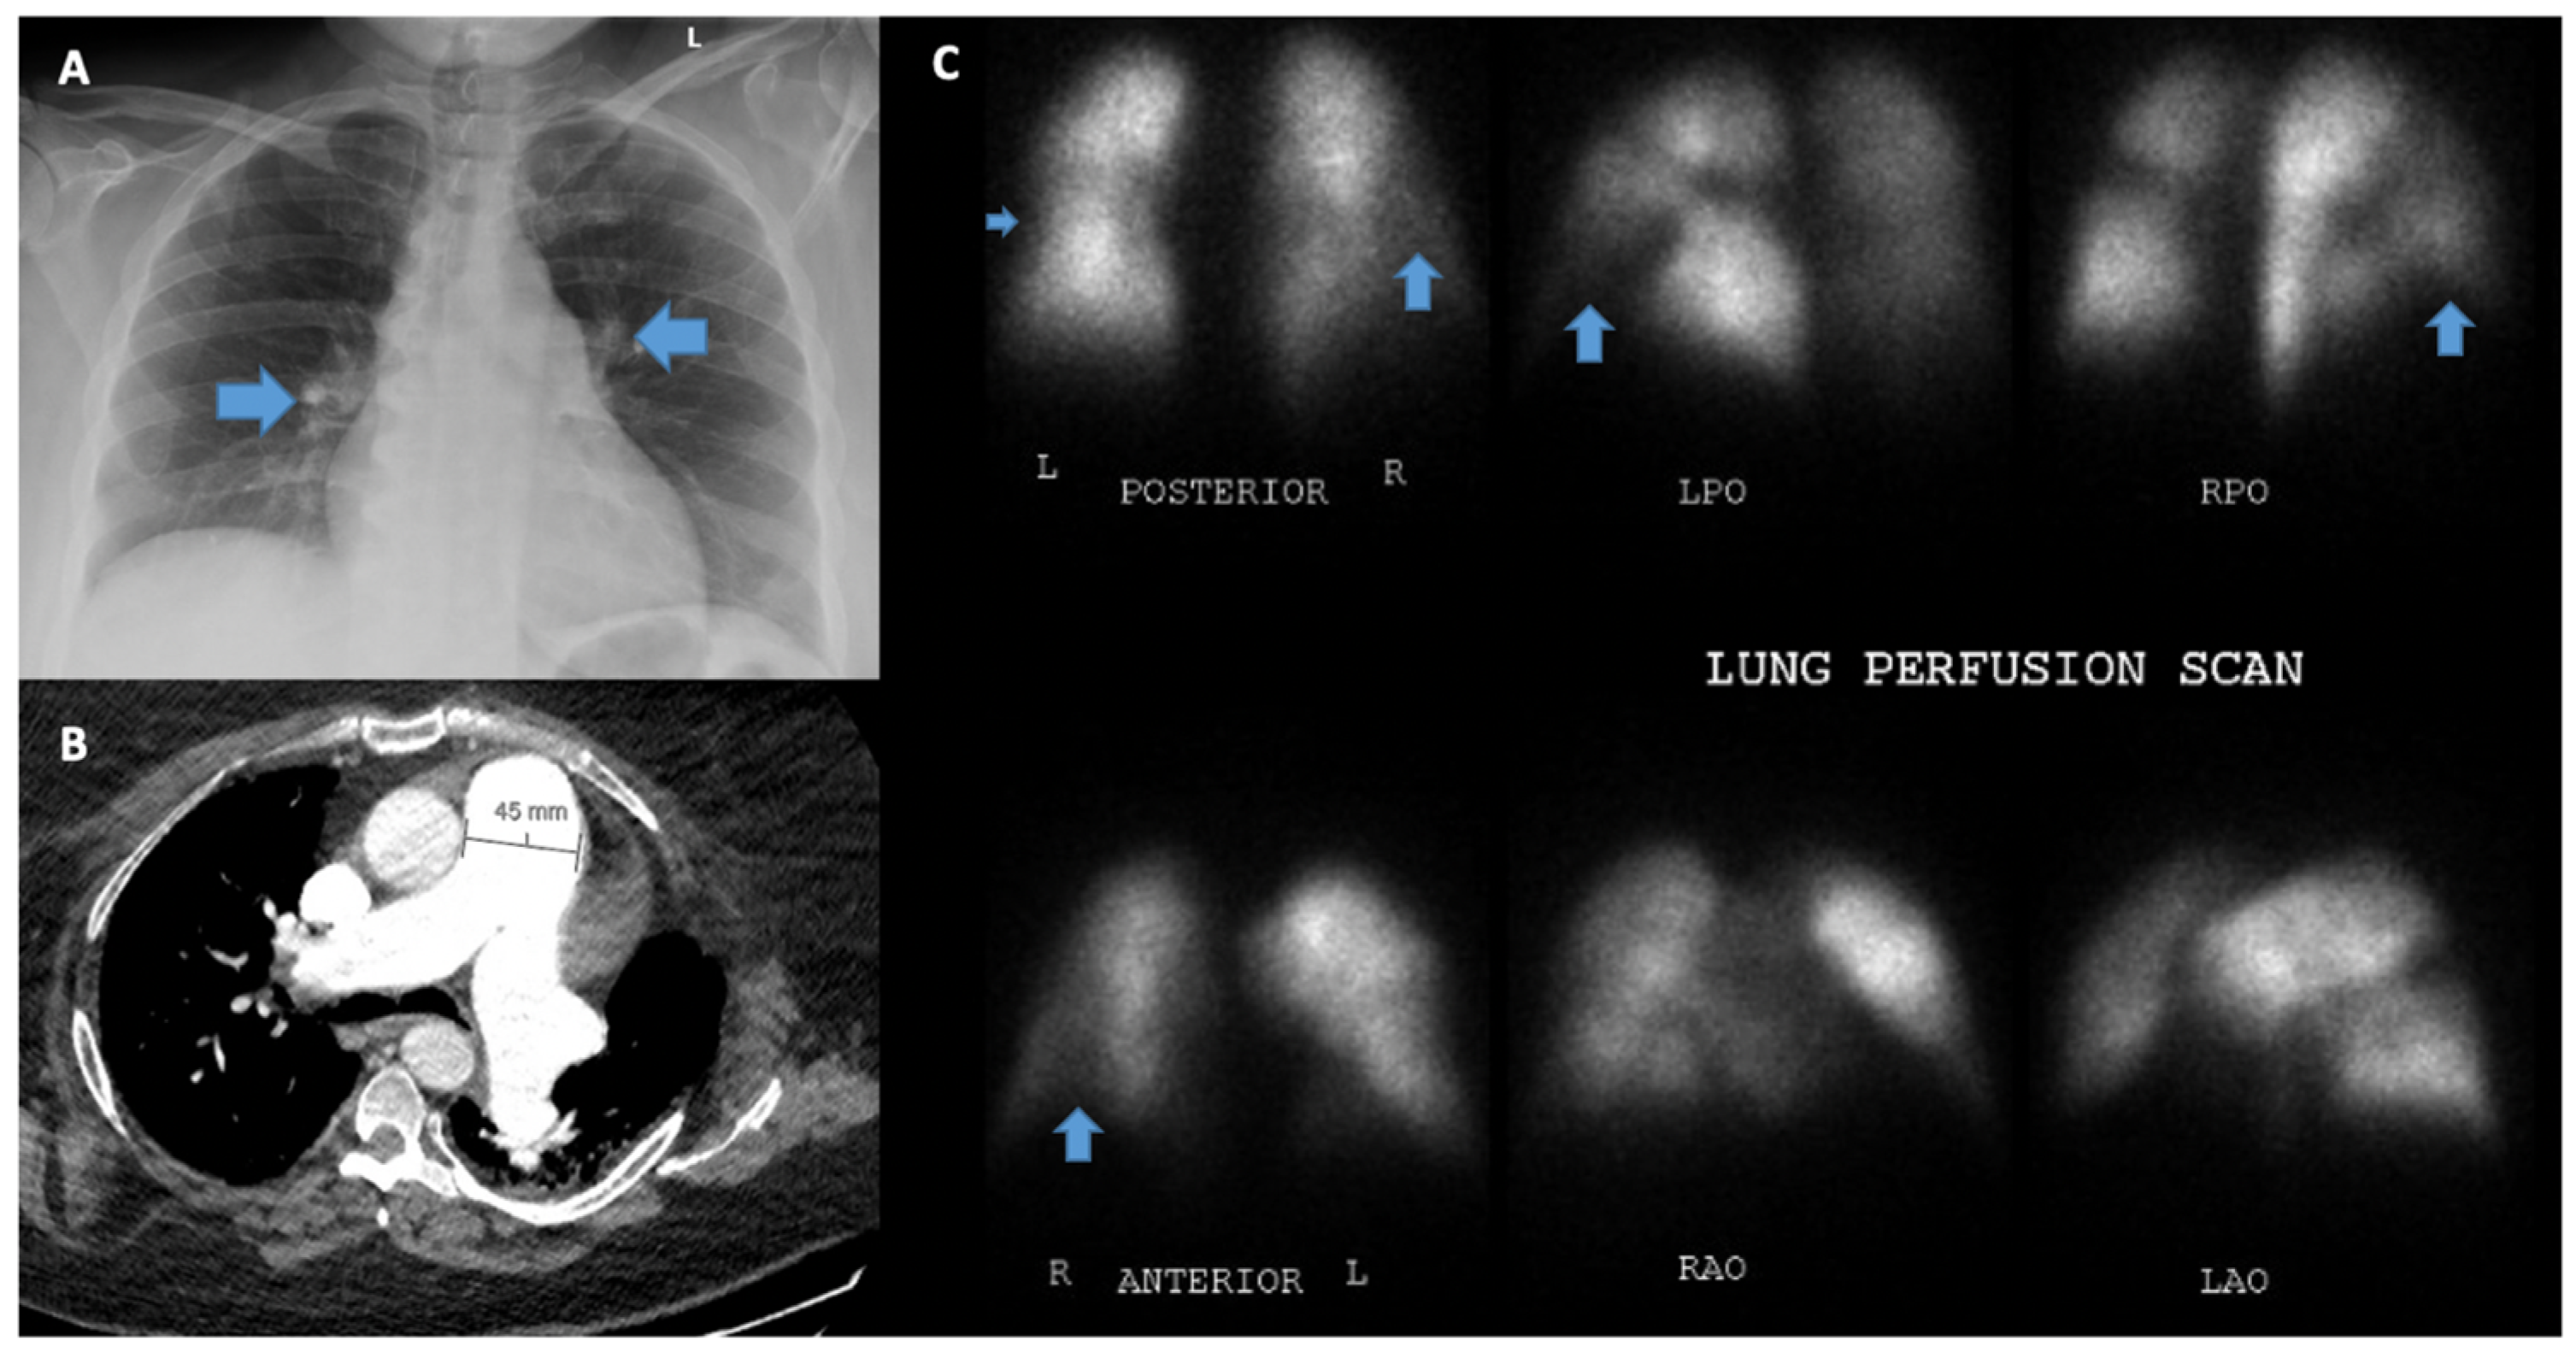

5.4. Chest X-ray

5.8. Ventilation/Perfusion Scanning (V/Q)

| CT chest [18] | 74–79% | 81–83% | CT chest allows for comprehensive evaluation of the pulmonary vasculature and lung parenchyma. | Radiation exposure. |

| VQ scan [19,20] | 90–100% | 94–100% | Allows us to distinguish CTEPH from other forms of PH, negative test helpful for ruling out CTEPH. | Low utility in diagnosing causes of PH other than thromboembolic disease. |